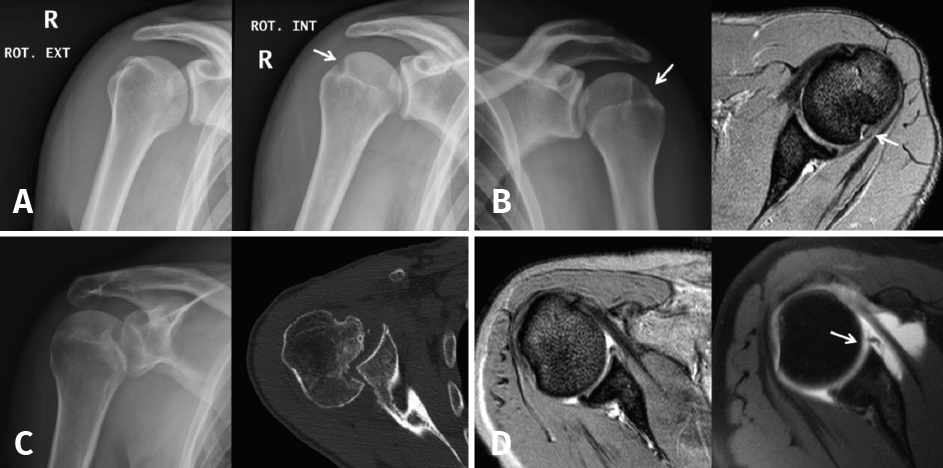

Small Hill-Sachs lesions (HSLs) in AP projection are only visualized with the shoulder in internal rotation (Figure 5A and B), while larger lesions can be seen in both internal rotation and external rotation(20) - the axillary projection affording better visualization of HSLs, however. For assessing glenoid bone loss, it is advisable to use an axillary projection or modified Bernageau projection, with a sensitivity and specificity of over 90%(20,21).

Figure 5. A and B: two cases of patients with Hill-Sachs lesions. A: comparison showing that it is easier to visualize the defect with the shoulder in internal rotation, especially in the case of a small defect; B: the same Hill Sachs lesion is observed on a comparative basis in the plain radiograph and MRI scan; C: computed axial tomography (CAT) view of a reverse Hill-Sachs lesion; D: ALPSA type lesion in conventional magnetic resonance imaging (MRI) and arthro-MRI. The latter technique is useful in the event of diagnostic doubt, since it offers more precise information about the type and characteristics of the capsulolabral lesion.

If these bone lesions are visible on plain radiographs, they can be assumed to be of considerable size; a CAT study therefore would be indicated to quantify the defect.

Three-dimensional reconstructions afford valuable information about the morphology of the glenoid cavity, as well as precise measurement of the size, location and depth of the defects of the humeral head (Figure 5C) and glenoid cavity(19,22) - these being decisive factors for the planning of surgery.

Arthro-MRI with intraarticular gadolinium contrast offers greater sensitivity and specificity in the diagnosis of lesions of the labrum than conventional MRI without contrast injection(19), though it is not a necessary routine test provided the MRI images are analysed by an experienced professional. It is reserved for those cases in which conventional MRI poses doubts (Figure 5D), or in patients with postsurgical relapse.